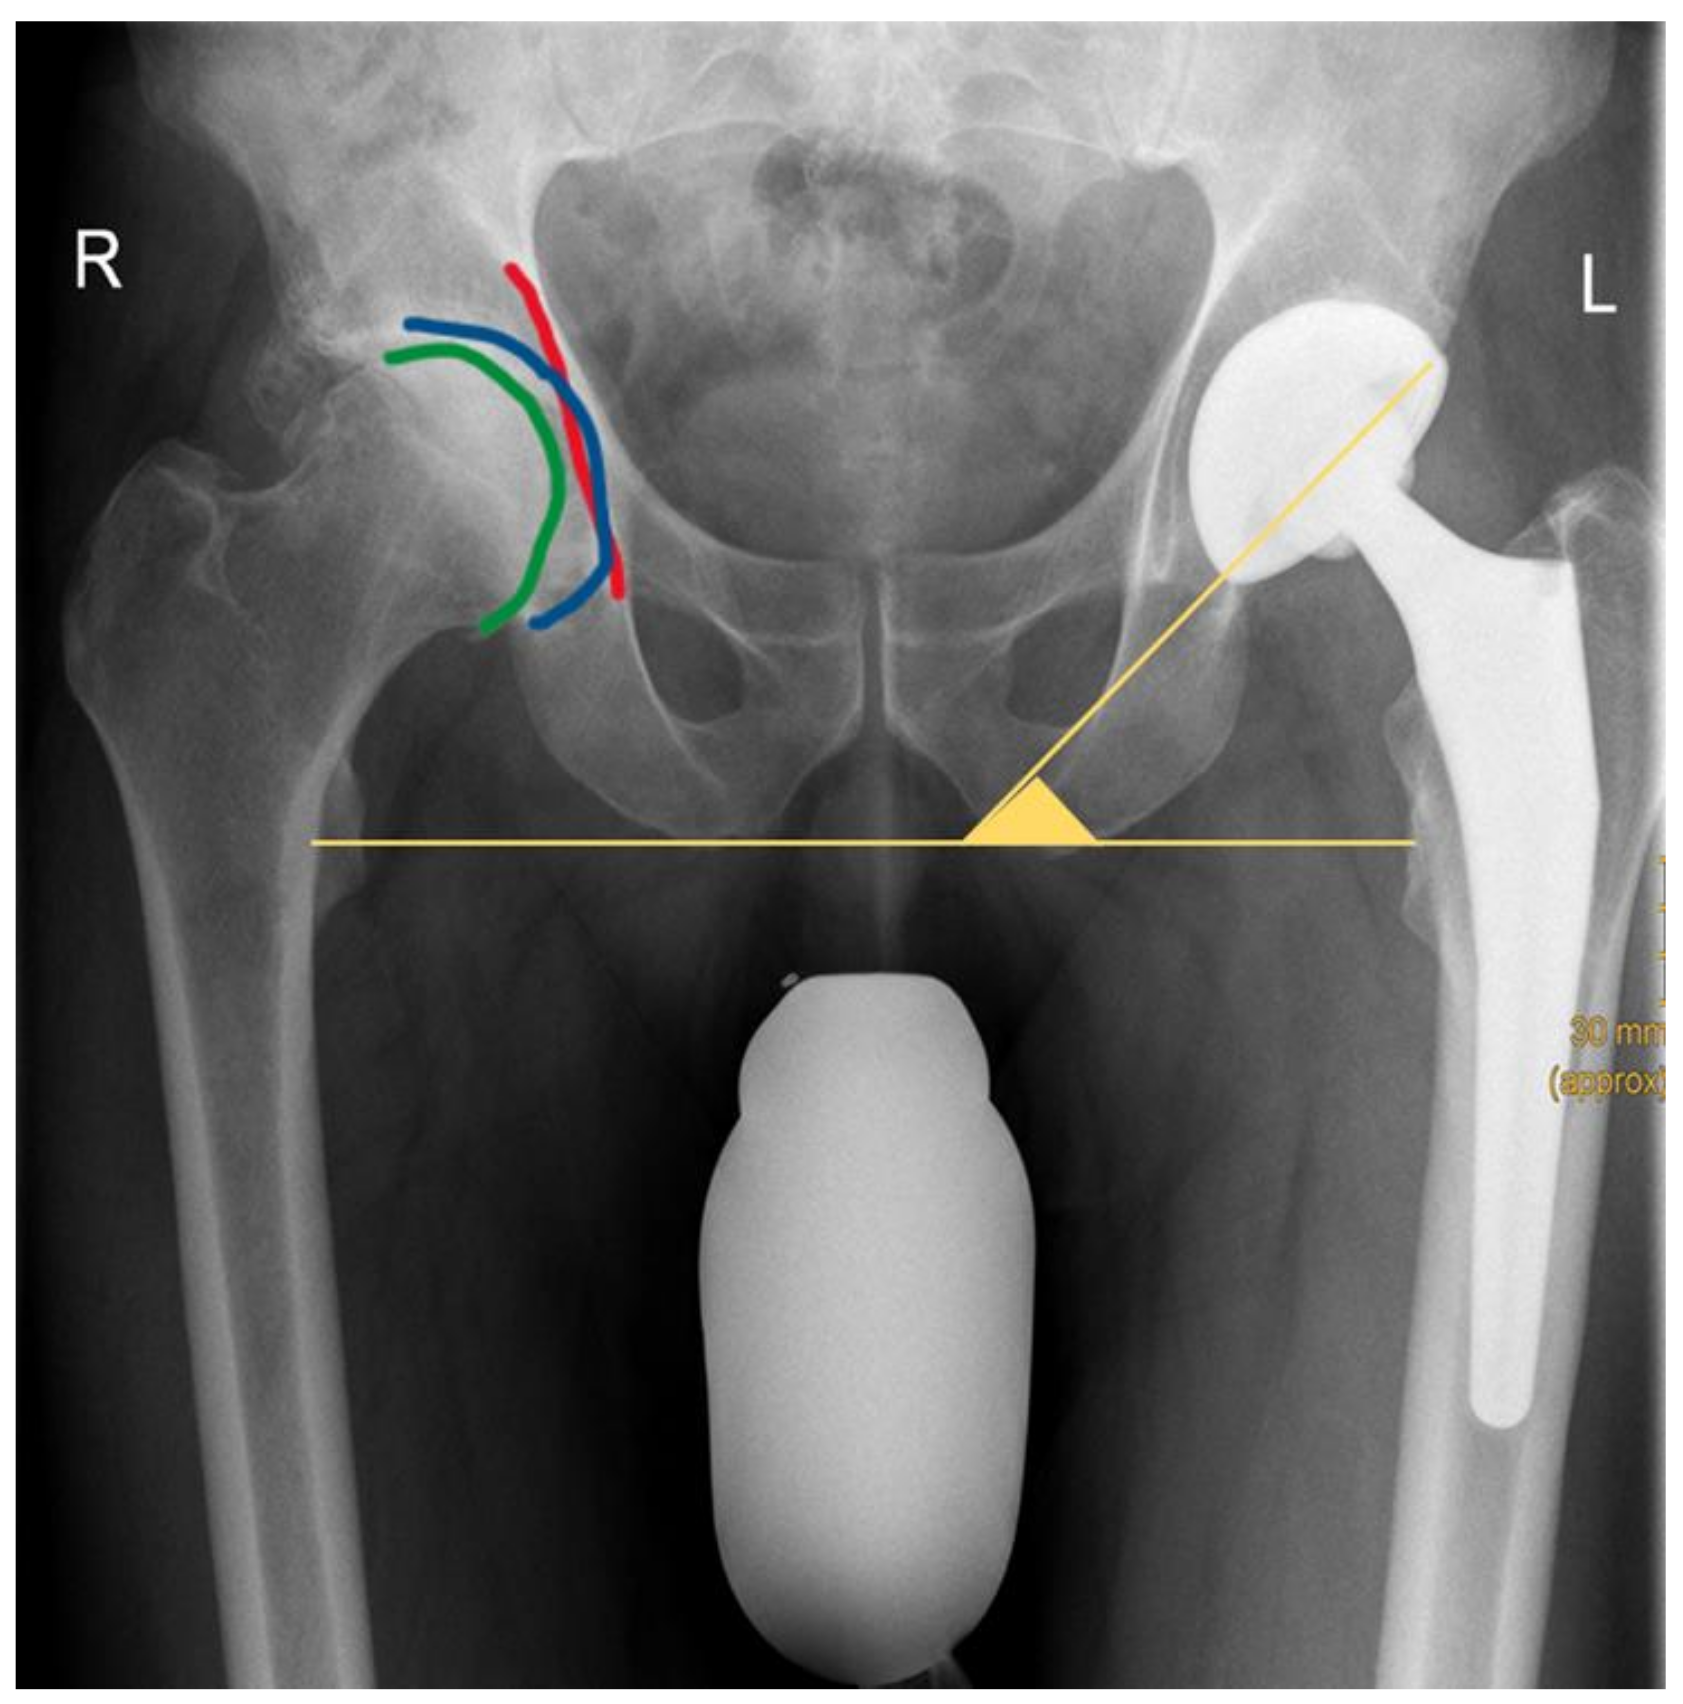

| LCEA (mean ± SD) | 40.41° ± 9.82° | 55.09° ± 9.64° | <0.00 |

| Sharp (mean ± SD) | 36.44° ± 5.15° | 34.04° ± 4.81° | <0.00 |

| Tönnis (mean ± SD) | 6.16° ± 5.70° | 3.12° ± 5.89° | <0.00 |

| Acetabular depth (mean ± SD) | 24.73 mm ± 4.01 mm | 27.92 mm ± 4.67 mm | <0.00 |

| ADWR (mean ± SD) | 334.60 ± 43.33 | 388.50 ± 61.22 | <0.00 |

| Change of FO (preoperative vs. postoperative) (mean ± SD) | 4.11 mm ± 7.66 mm | 0.71 mm ± 8.21 mm | <0.00 |

| FO, preoperative (mean ± SD) | 42.94 mm ± 7.20 mm | 46.22 mm ± 7.57 mm | <0.00 |

| FO, postoperative | 47.05 mm ± 5.38 mm | 45.52 mm ± 4.46 mm | 0.03 |

| LLD, preoperative (mean ± SD) | 4.49 mm ± 4.24 mm | 7.65 mm ± 6.76 mm | <0.00 |

| LLD, postoperative (mean ± SD) | 4.87 mm ± 4.12 mm | 5.41 mm ± 5.00 mm | 0.41 |

| AGVD (mean ± SD) | 108.59 mm ± 13.75 mm | 101.91 mm ± 14.36 mm | <0.00 |

| GT/ASIS (mean ± SD) | 1.19 ± 0.07 | 1.13 ± 0.07 | <0.00 |

| Cup inclination | 36.57° ± 6.57° | 38.13° ± 6.82° | 0.04 |